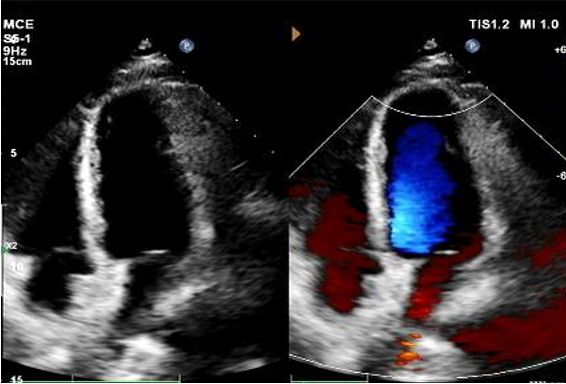

1-годовое эхо:

No visible disc structures – replaced by 8mm tissue thickening at the septal implant site.

Zero residual shunt (rest or post-Valsalva).

Полное поглощение устройства подтверждено.